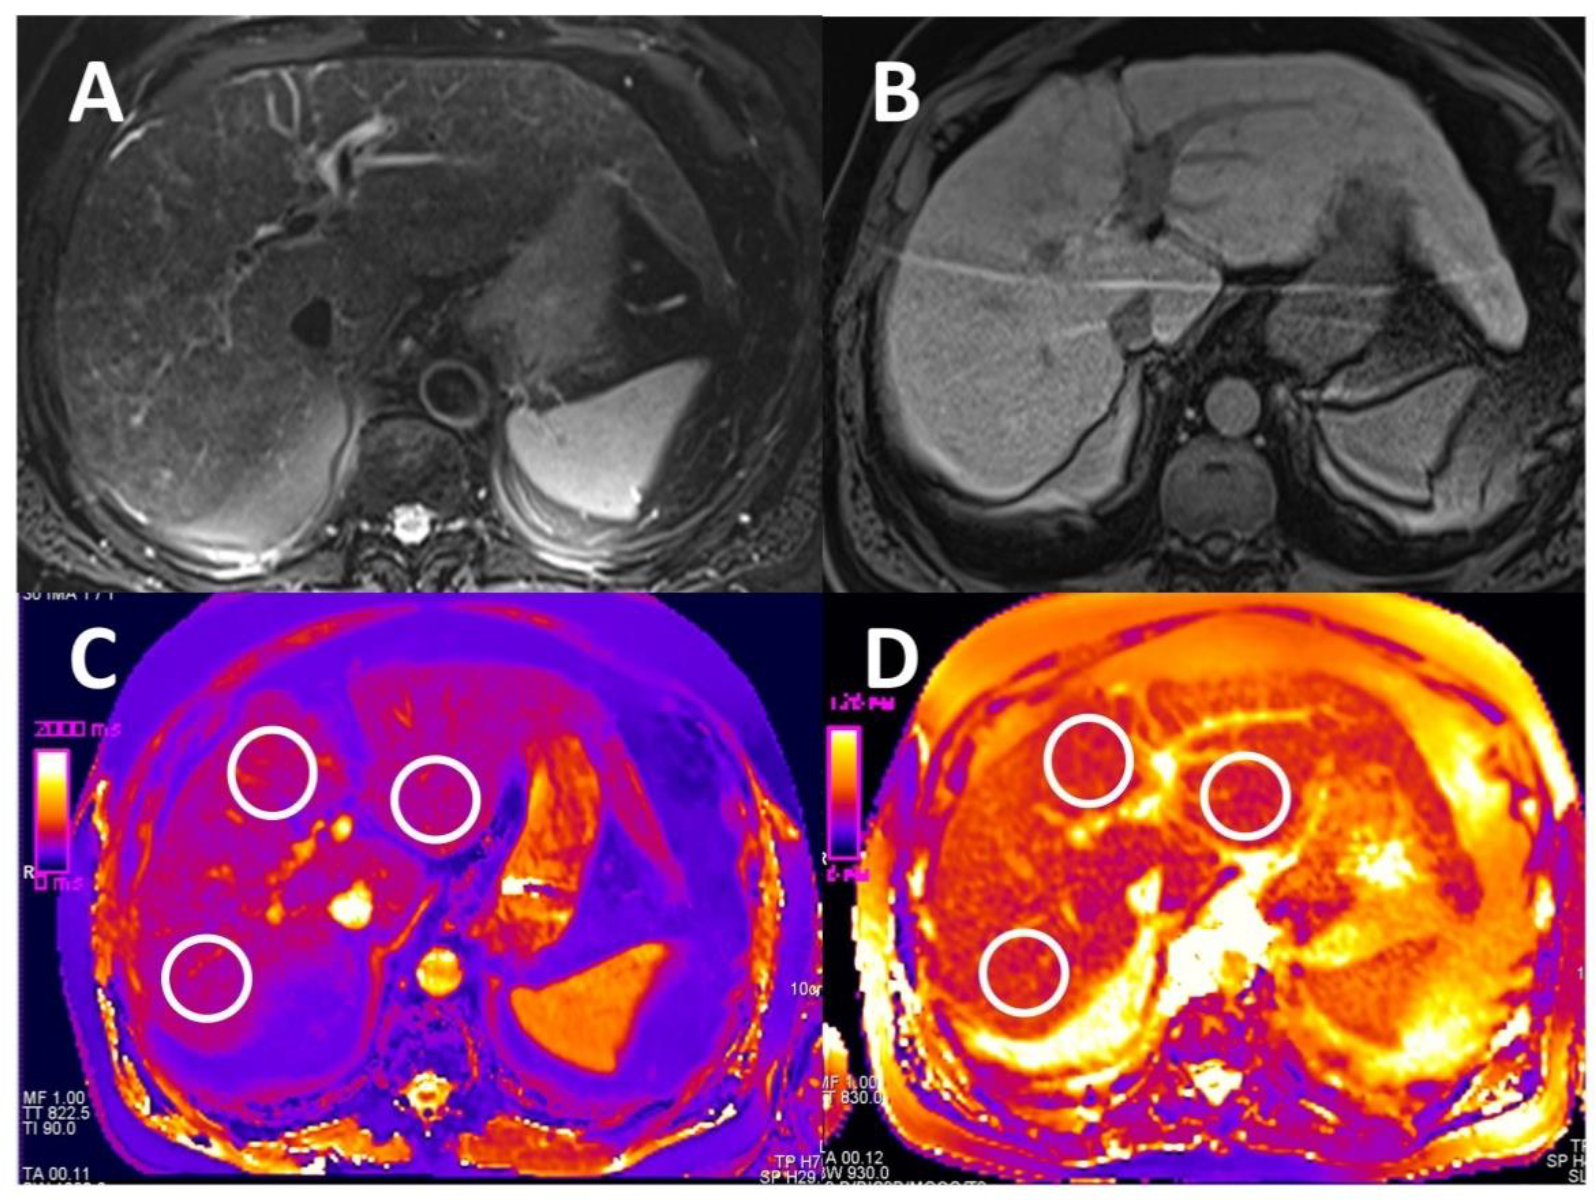

2.4. Image Analysis

2.4.1. T1 and T2 Relaxometry